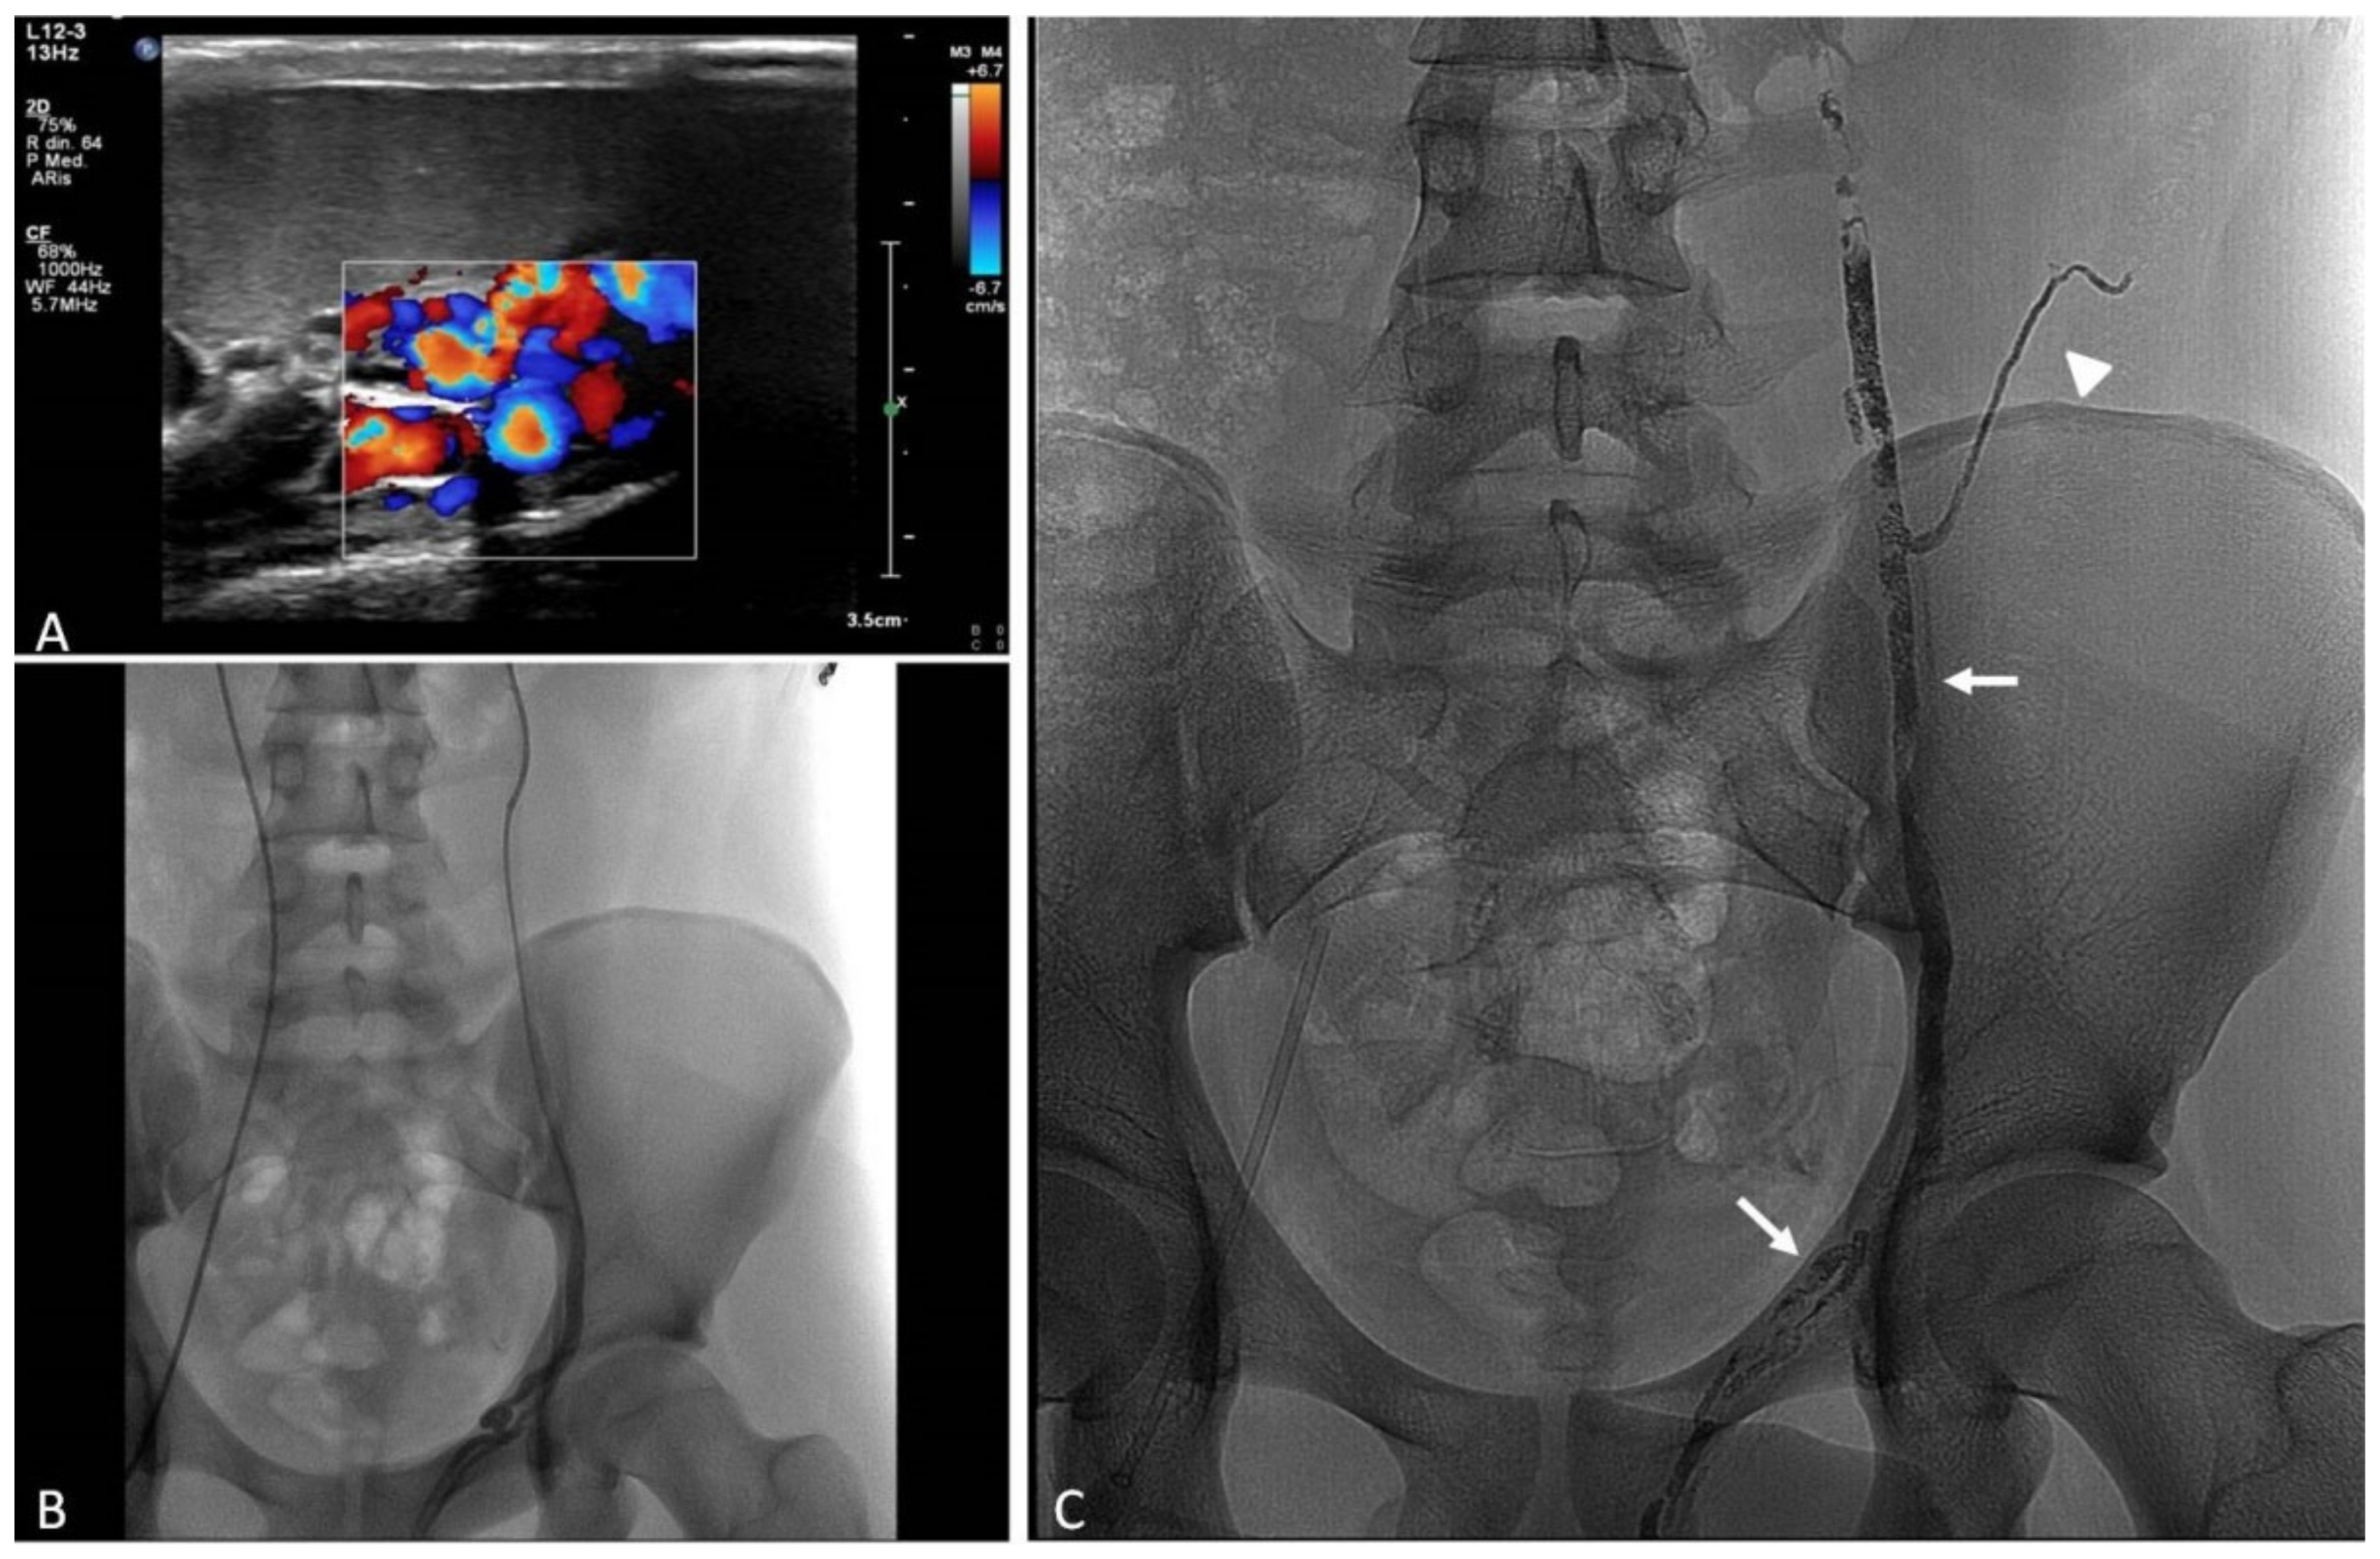

13. Sclero-Embolization of Male Varicocele

13.1. Indications

13.2. Techniques

13.3. Clinical Outcomes